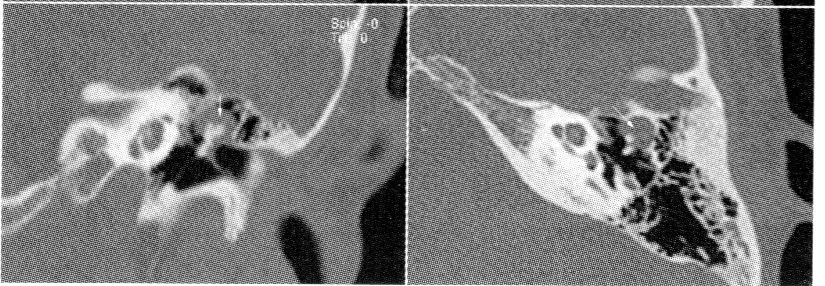

50 歲男性主訴左耳反覆耳漏及聽力損失超過 10 年,局部檢查後,安排高解析度電腦斷層攝影,結果如下:在上鼓室有一軟組織包圍聽小骨(如下圖),最有可能之診斷為何?

本題提供兩張高解析度顳骨電腦斷層(HRCT)影像(冠狀面及軸位面)。影像所見:

- 左側:上鼓室(epitympanum)及 Prussack's space 內可見一不依重力分布(non-dependent)的軟組織密度病灶,包圍聽小骨(ossicles),符合膽脂瘤典型位置

- 聽小骨(malleus、incus)被軟組織病灶包繞,可見不同程度的骨質侵蝕(ossicular erosion)

- 右側對照影像可見正常含氣中耳腔及完整聽小骨

- 鼓室蓋(tegmen tympani)與鼓室硬化板(scutum)在病灶側有侵蝕跡象

此影像所見與膽脂瘤的典型 HRCT 表現高度吻合:上鼓室軟組織病灶伴聽小骨侵蝕。